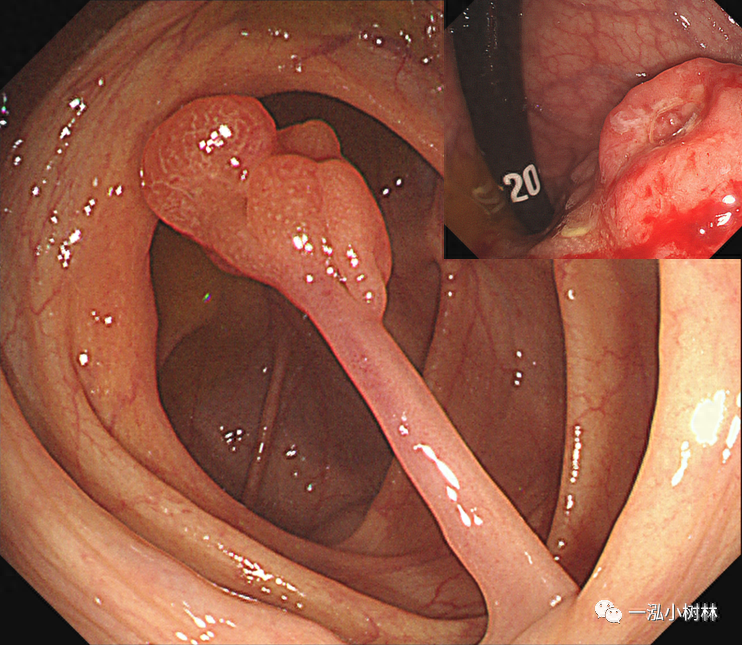

图13 结肠长蒂息肉